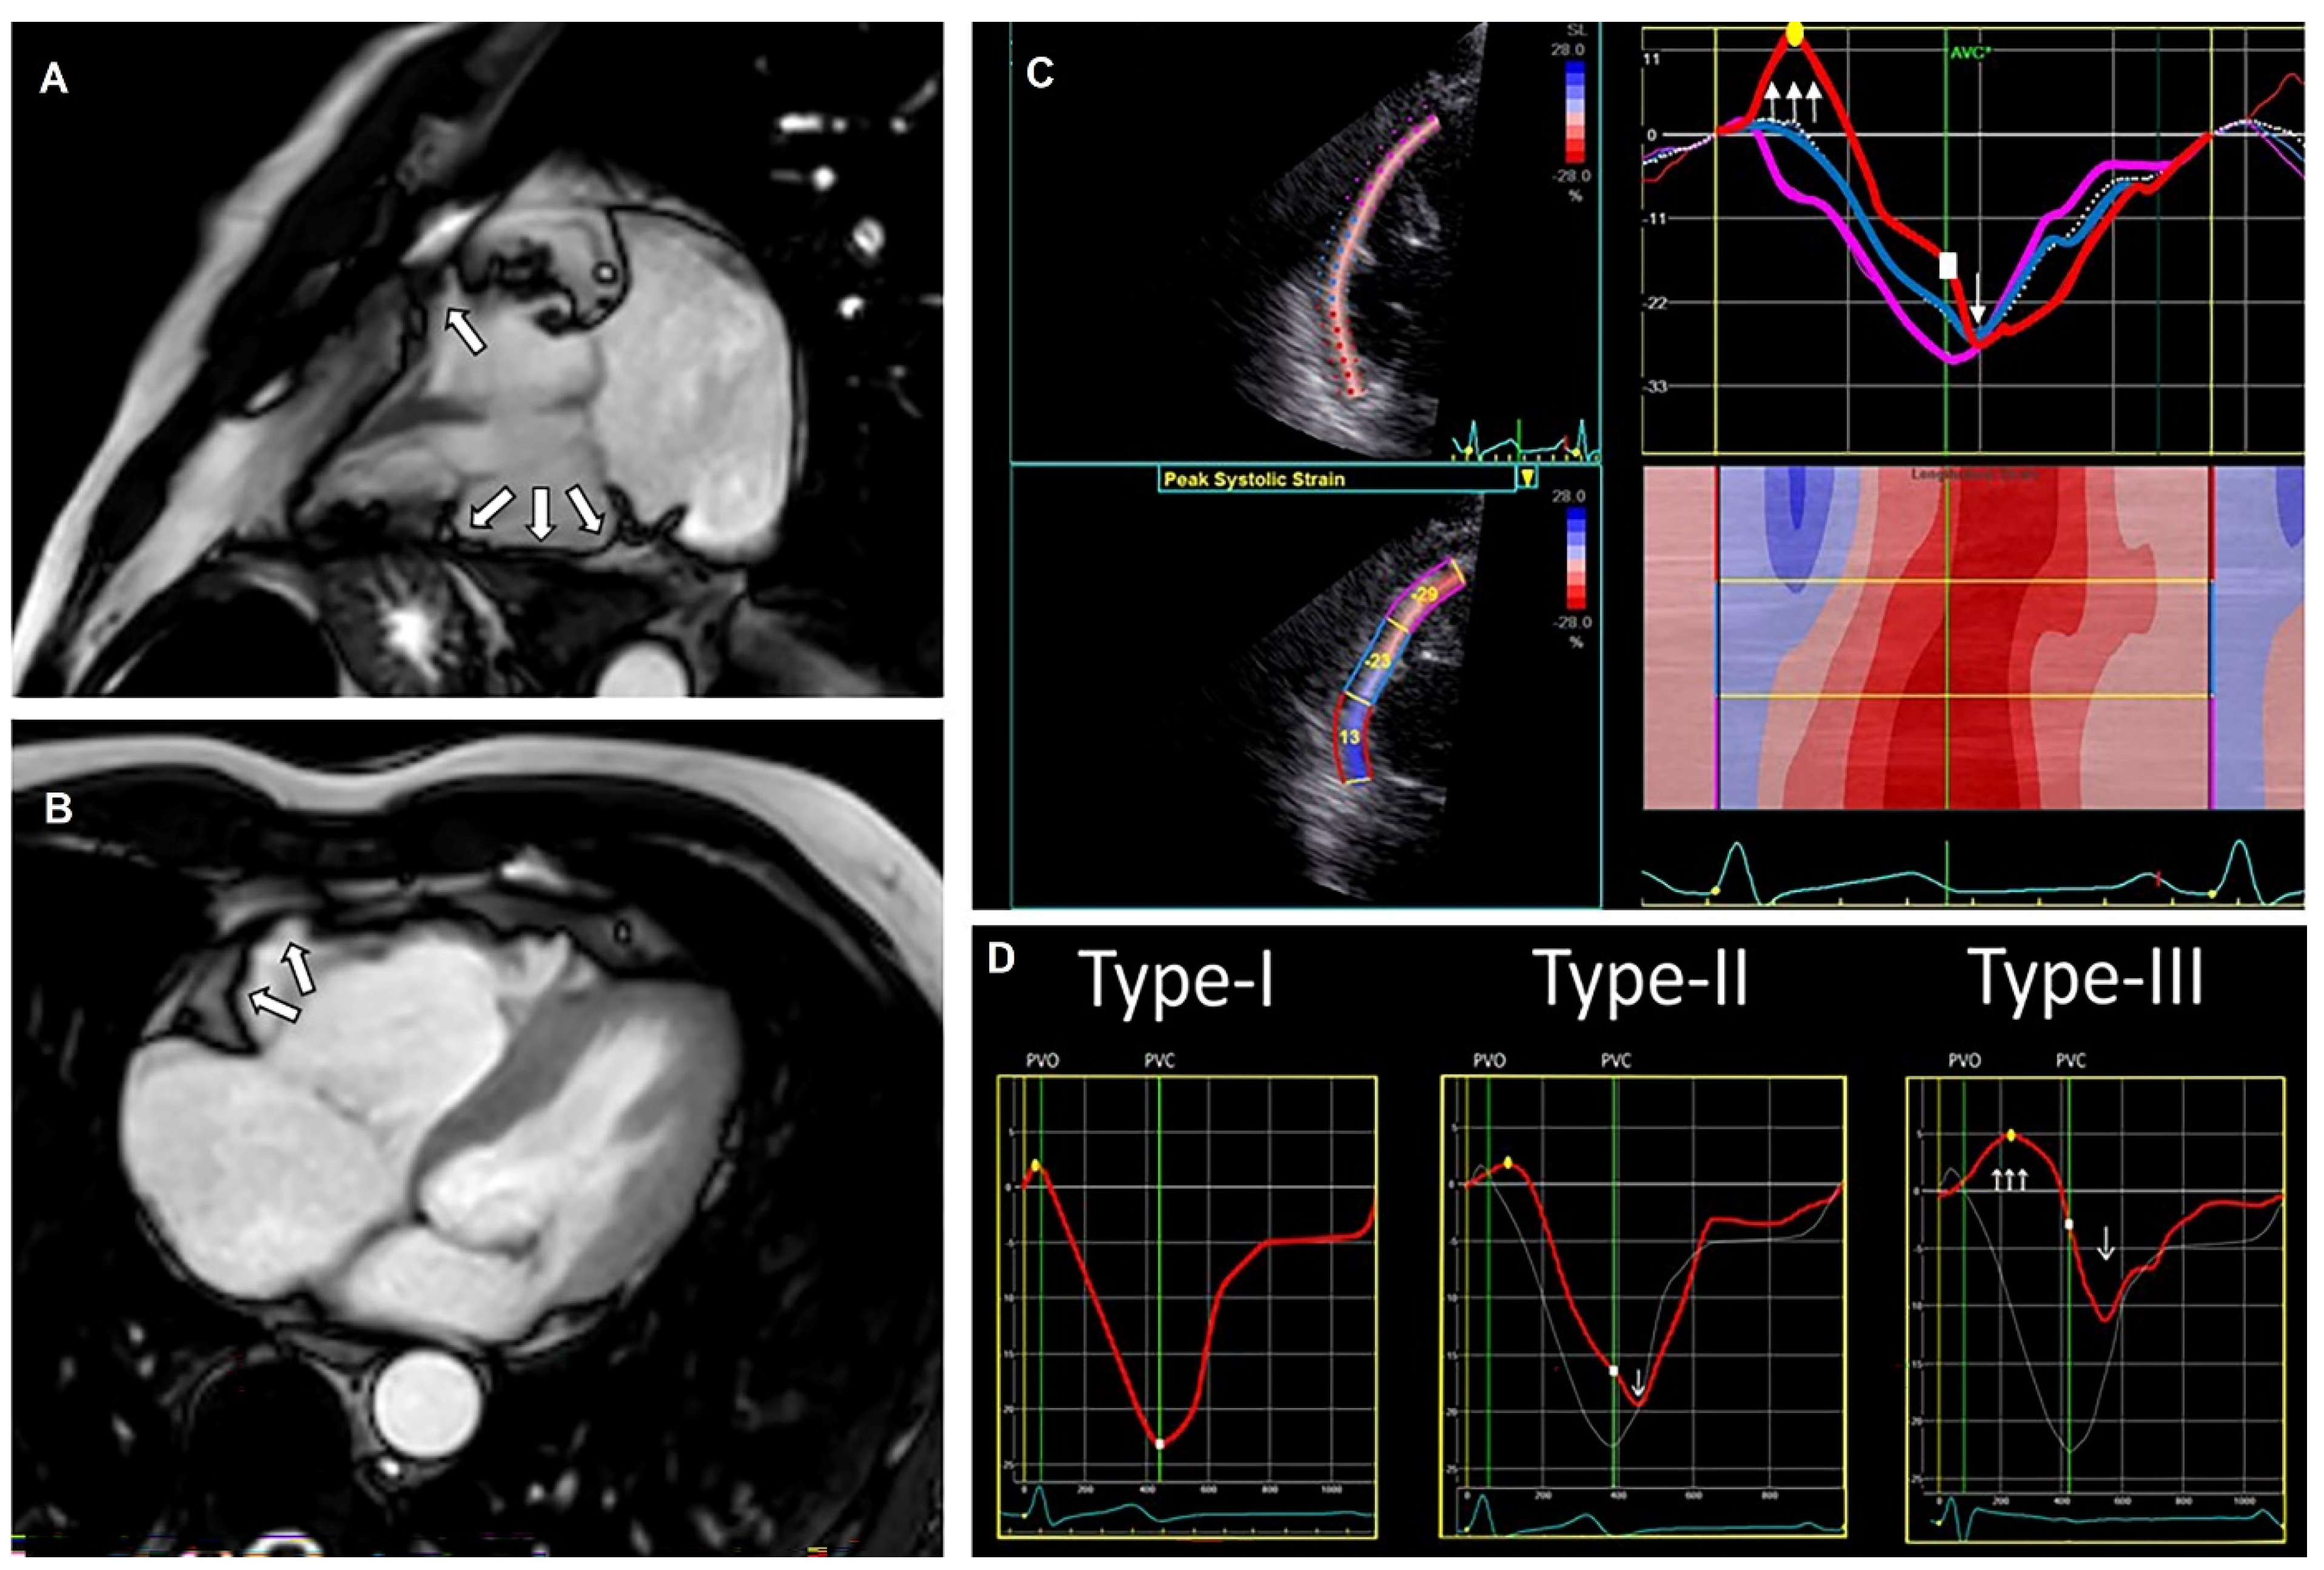

- Groeneveld, S.A.; van der Ree, M.H.; Taha, K.; de Bruin-Bon, R.H.A.; Cramer, M.J.; Teske, A.J.; Bouma, B.J.; Amin, A.S.; Wilde, A.A.M.; Postema, P.G.; et al. Echocardiographic Deformation Imaging Unmasks Global and Regional Mechanical Dysfunction in Patients with Idiopathic Ventricular Fibrillation: A Multicenter Case-Control Study. Heart Rhythm 2021, 18, 1666–1672. [Google Scholar] [CrossRef]

- Mast, T.P.; Teske, A.J.; Walmsley, J.; van der Heijden, J.F.; van Es, R.; Prinzen, F.W.; Delhaas, T.; van Veen, T.A.; Loh, P.; Doevendans, P.A.; et al. Right Ventricular Imaging and Computer Simulation for Electromechanical Substrate Characterization in Arrhythmogenic Right Ventricular Cardiomyopathy. J. Am. Coll. Cardiol. 2016, 68, 2185–2197. [Google Scholar] [CrossRef] [PubMed]

- Groeneveld, S.A.; Kirkels, F.P.; Cramer, M.J.; Evertz, R.; Haugaa, K.H.; Postema, P.G.; Prakken, N.H.J.; Teske, A.J.; Wilde, A.A.M.; Velthuis, B.K.; et al. Prevalence of Mitral Annulus Disjunction and Mitral Valve Prolapse in Idiopathic Ventricular Fibrillation Patients. J. Am. Heart Assoc. 2022, 11, e025364. [Google Scholar] [CrossRef]

- Dejgaard, L.A.; Skjølsvik, E.T.; Lie, Ø.H.; Ribe, M.; Stokke, M.K.; Hegbom, F.; Scheirlynck, E.S.; Gjertsen, E.; Andresen, K.; Helle-Valle, T.M.; et al. The Mitral Annulus Disjunction Arrhythmic Syndrome. J. Am. Coll. Cardiol. 2018, 72, 1600–1609. [Google Scholar] [CrossRef]